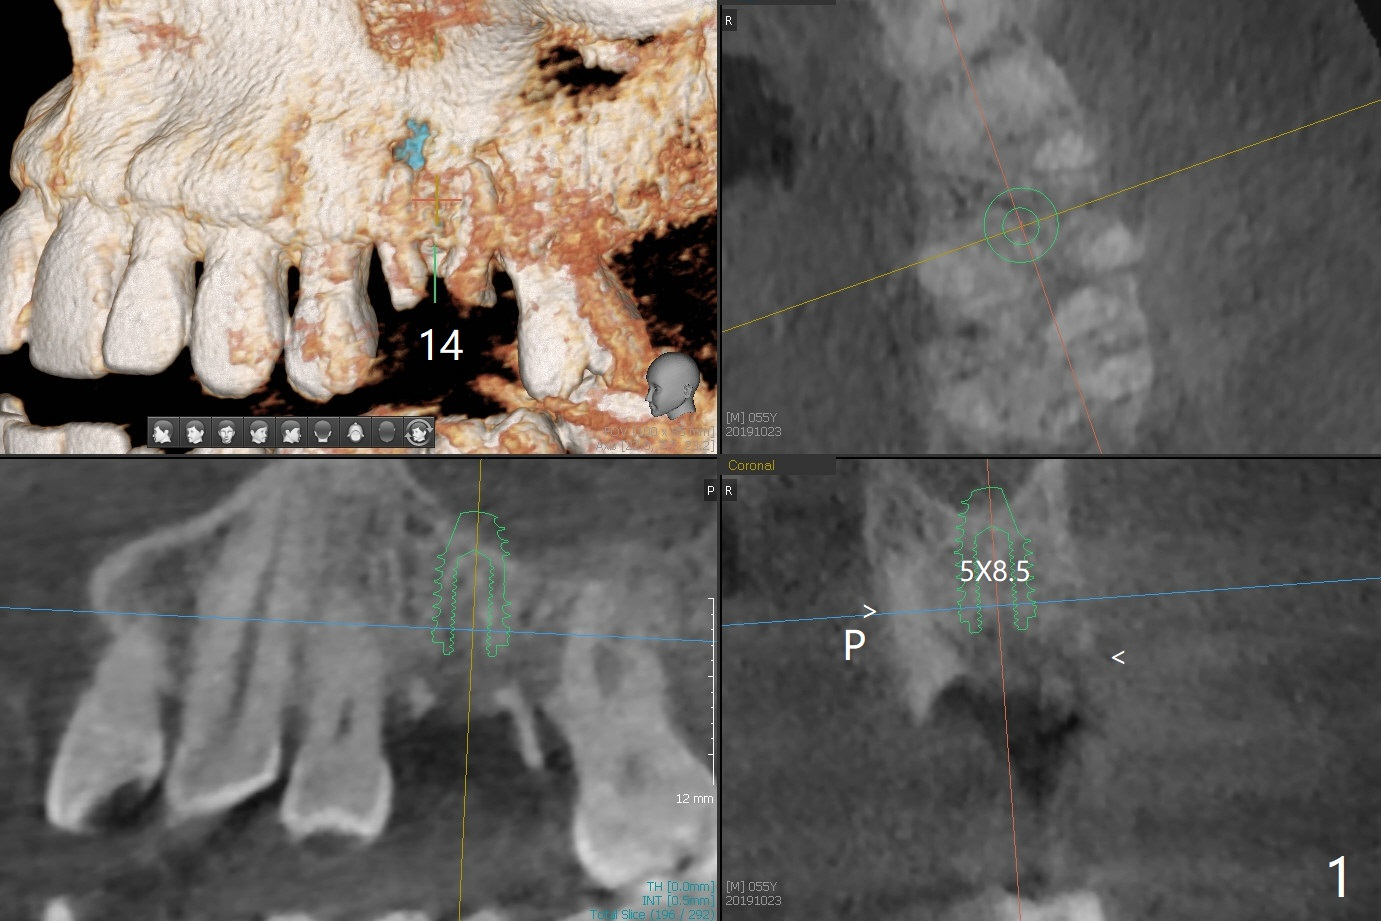

A 55-year-old man agrees to have the tooth #14 to be extracted for immediate implant. It appears that the palatal bone is lower than the buccal bone (Fig.1 arrowheads). If palatal shield is conducted (Fig.3 *), the implant can be longer (5x10 vs. 8.5 mm, Fig.2-4).